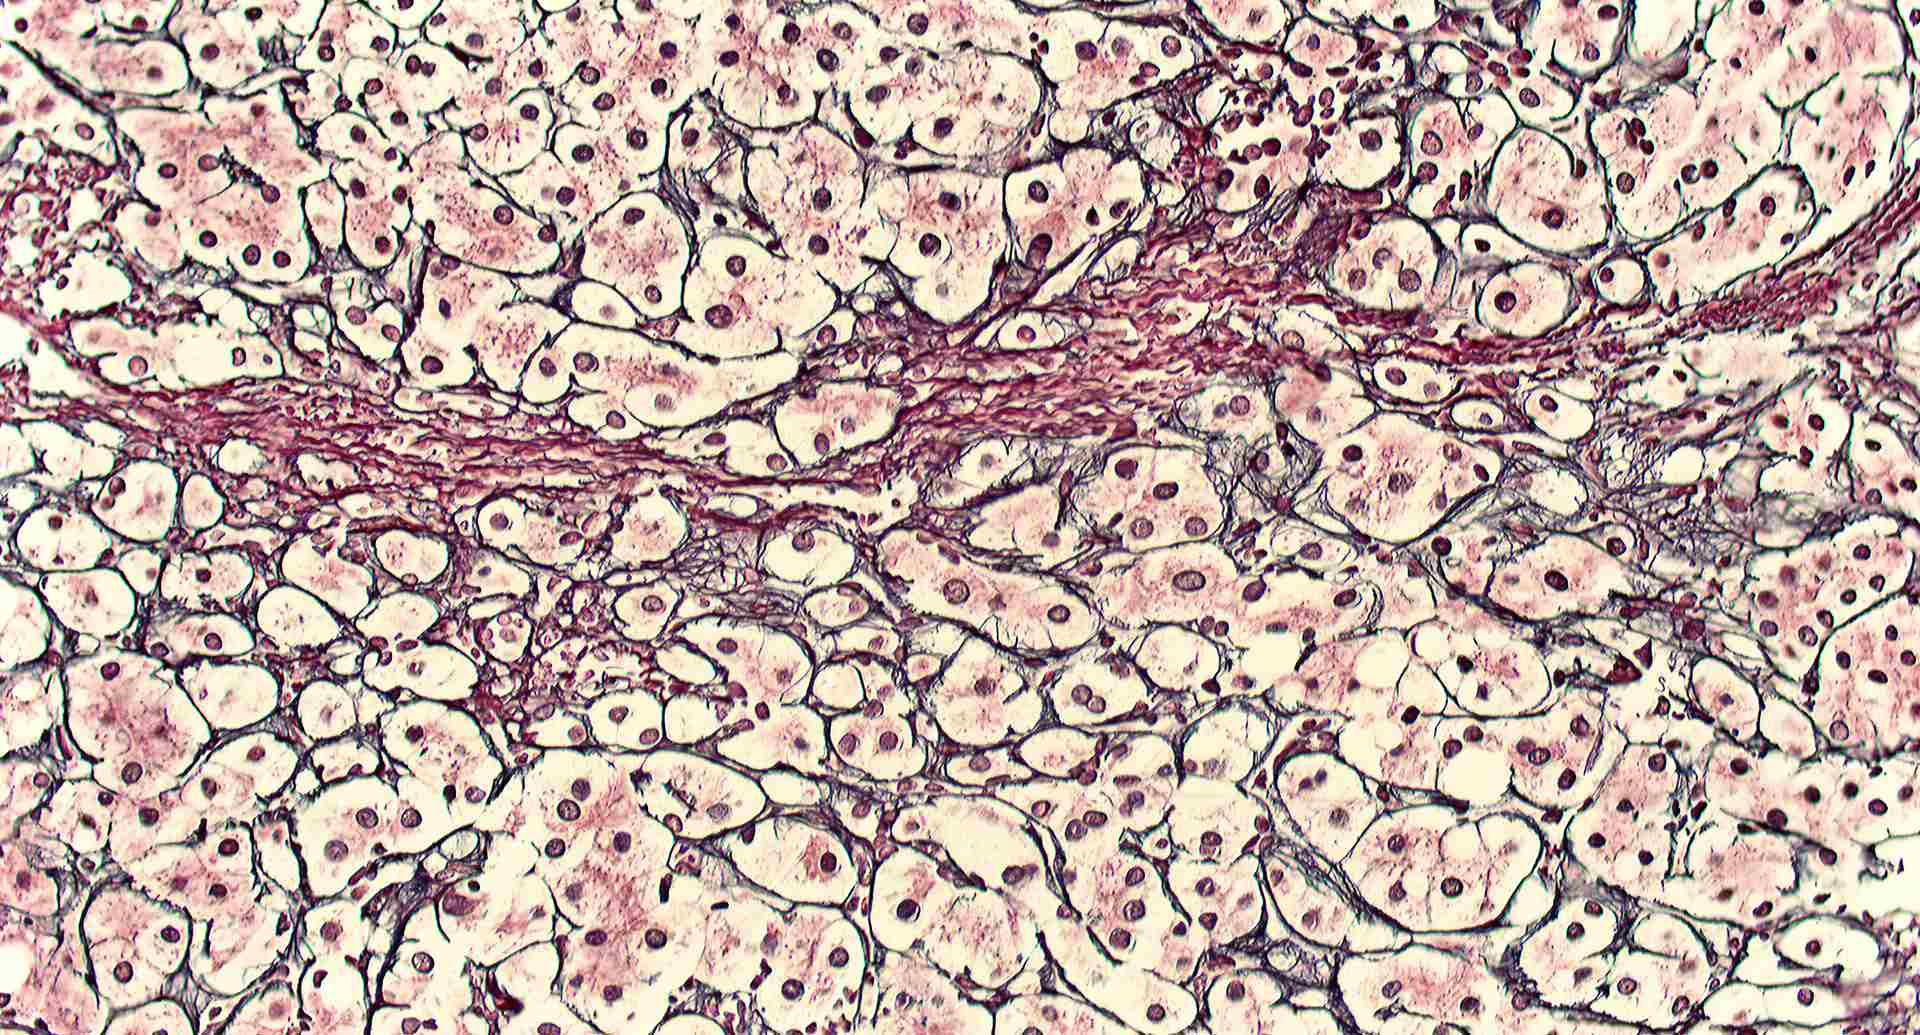

標本7

標本7の説明